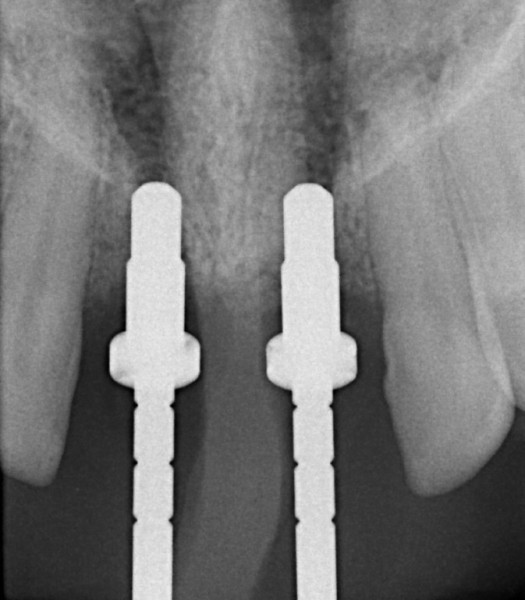

The CT scanner's imaging allows us to create custom made surgical guides specific to each patient.  These surgical guides allow the precise placement of dental implants for optimal functional and esthetic results.

CT Guided Custom Implant Placment

A Case with a Fractured Central Incisor